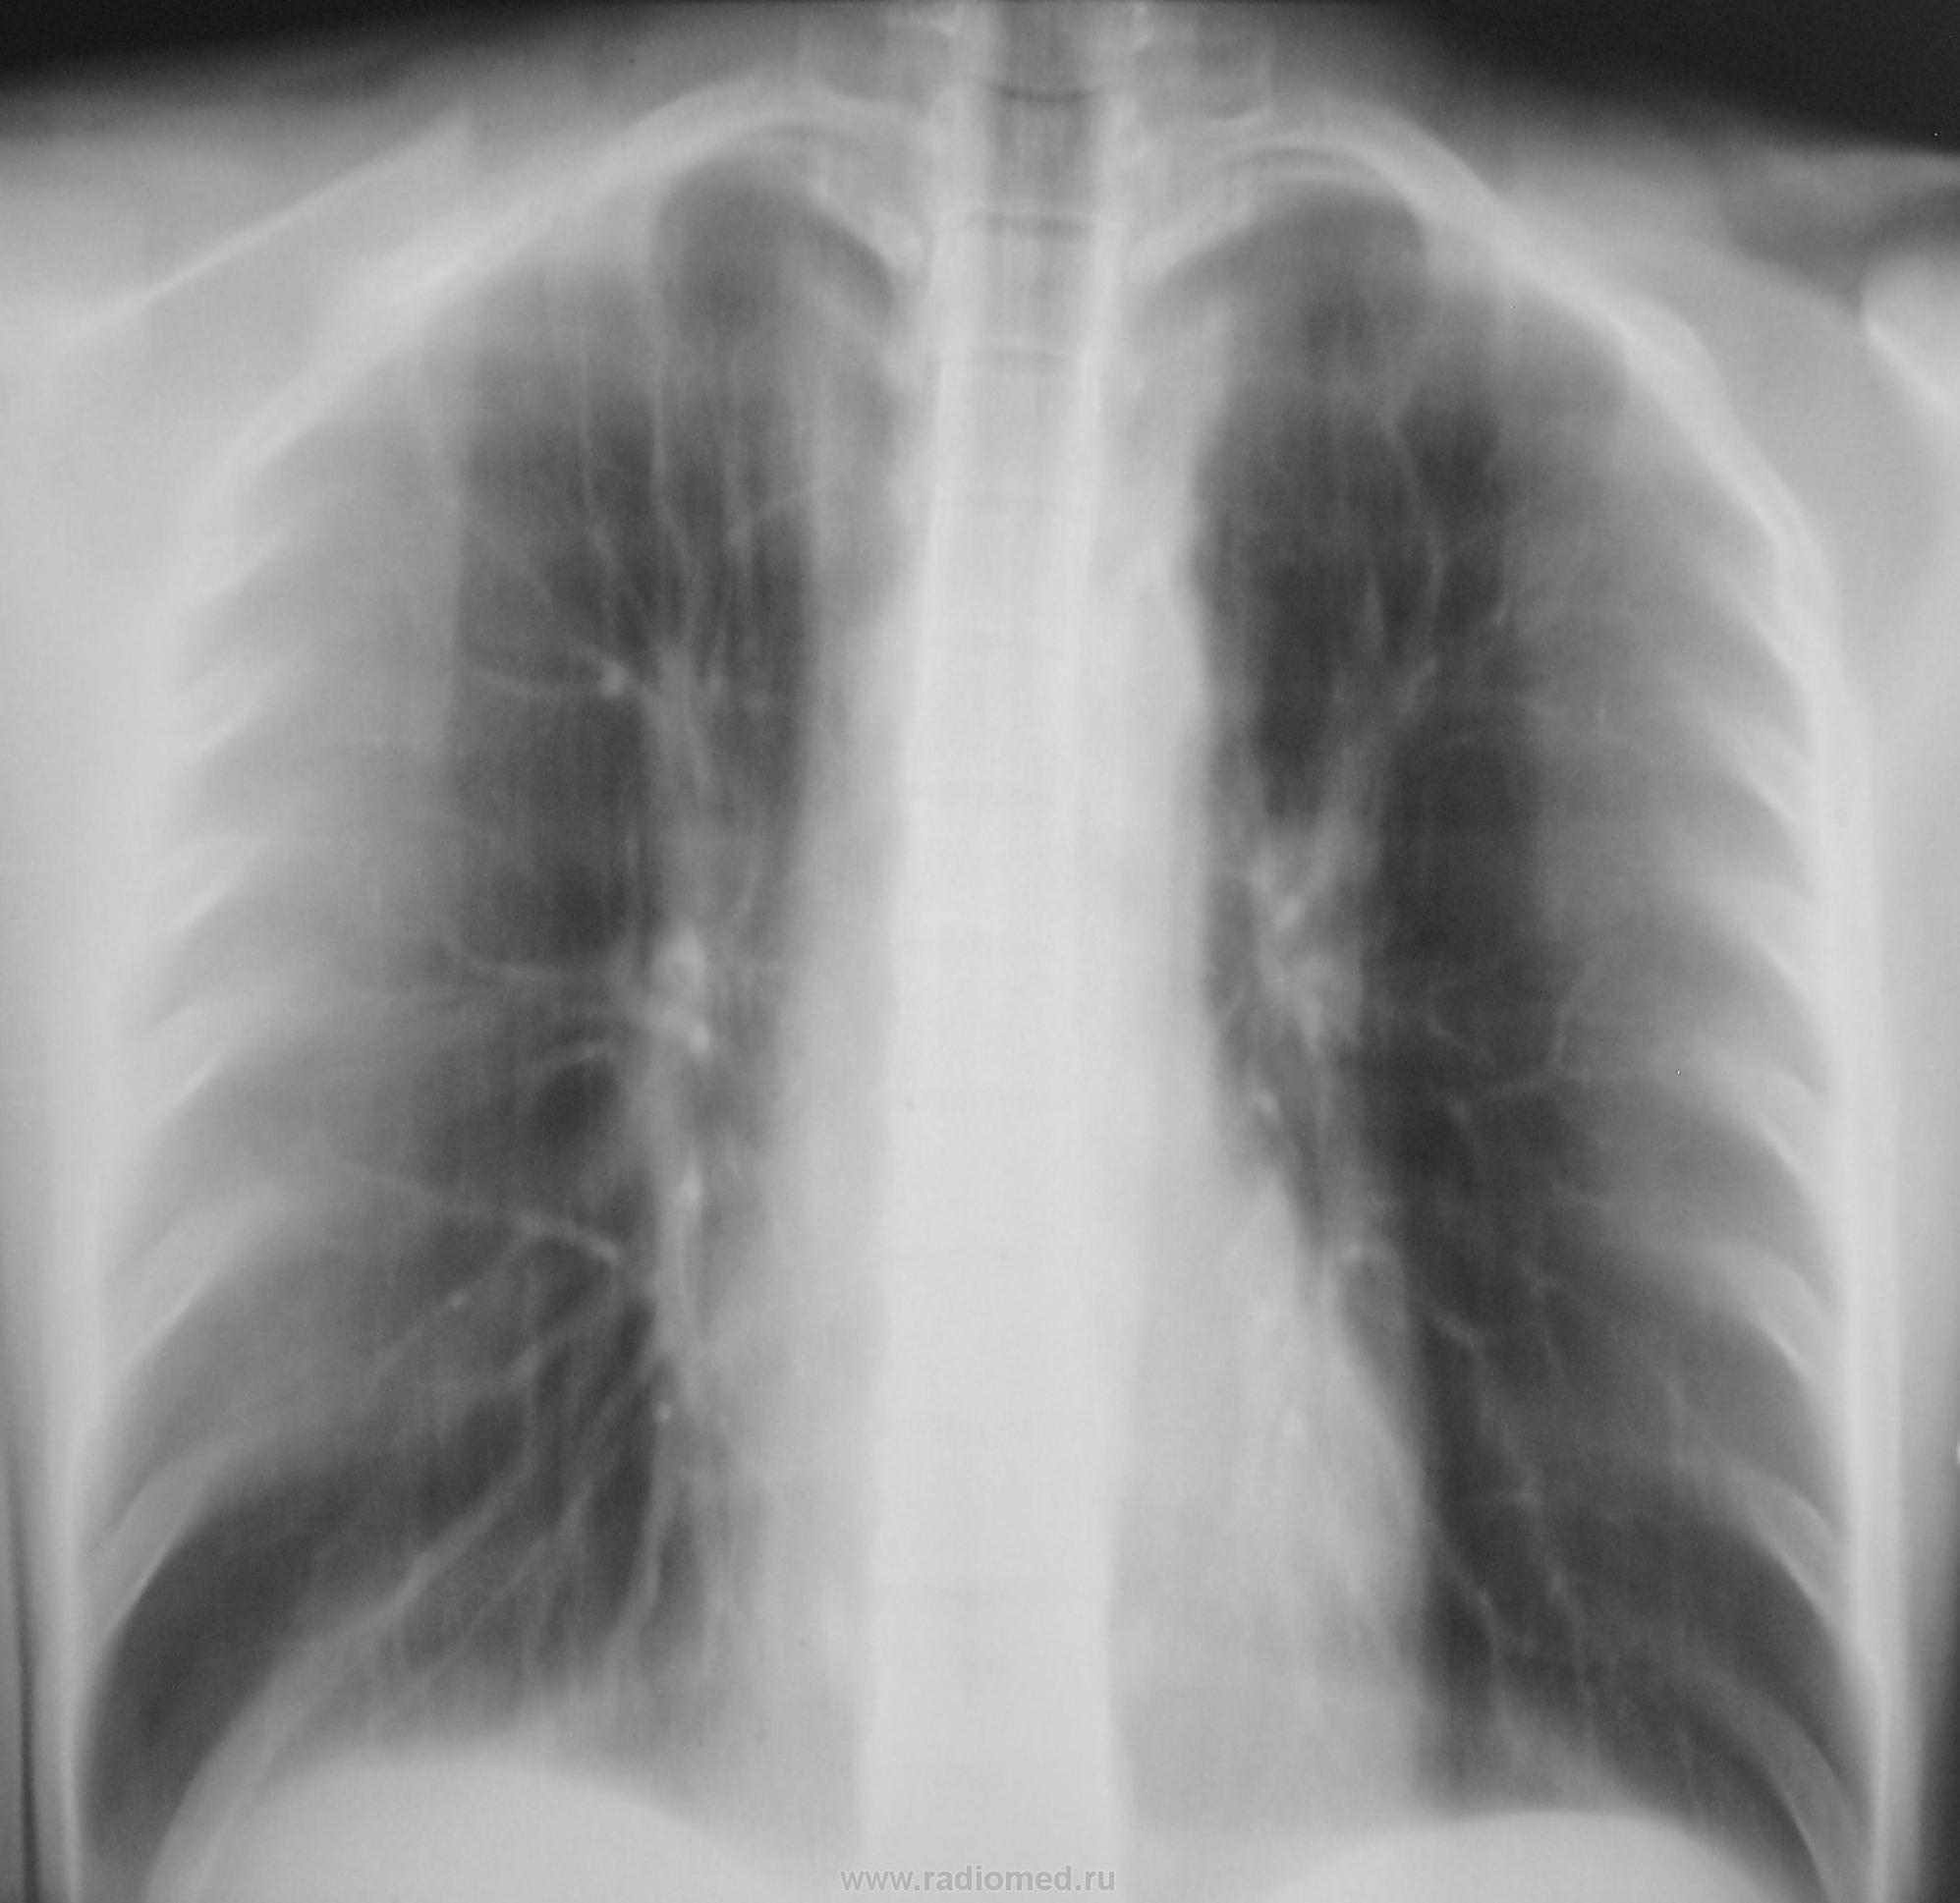

Произведена рентгенограмма в прямой проекции.

Да, у меня, как правило, "танец" начинается с верхушек.

Смотрите рисунок.  Заключение написано на снимке. Кроме очагов в легких, имеется увеличение паратрахеального лимфатического узла. В ПТД на лечение.  Nikolas

Дело в том, что этого пациента я зацепил еще год тому назад.

Снимки ниже.